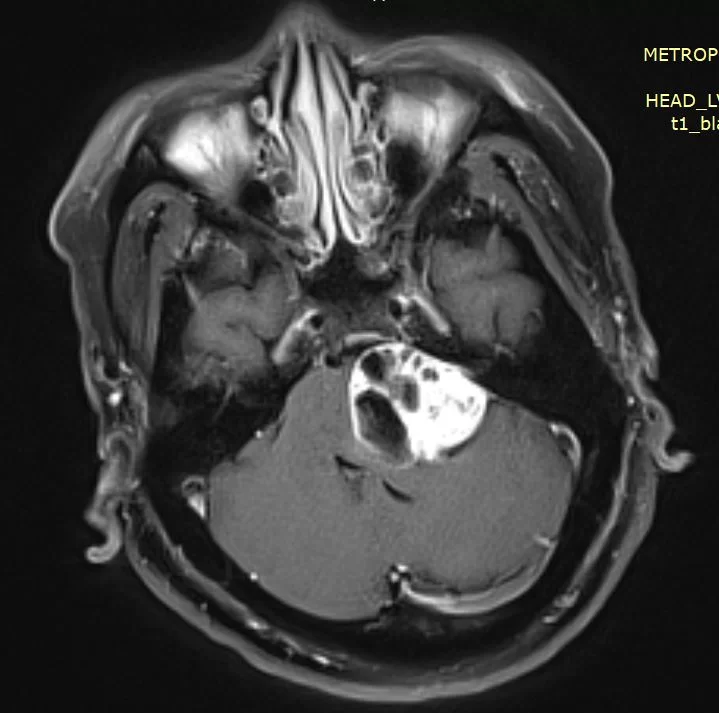

Μηνιγγίωμα Λιθοειδούς-Αποκλιματος (Petroclival)

Ασθενής γυναίκα, 37 ετών η οποία προοδευτικά παρουσίασε κεφαλαλγίες, διπλωπία, έκπτωση ακοής δεξιά, διαταραχές βάδισης και ημιπάρεση αριστερά. Ο απεικονιστικός έλεγχος με μαγνητική τομογραφία ανέδειξε